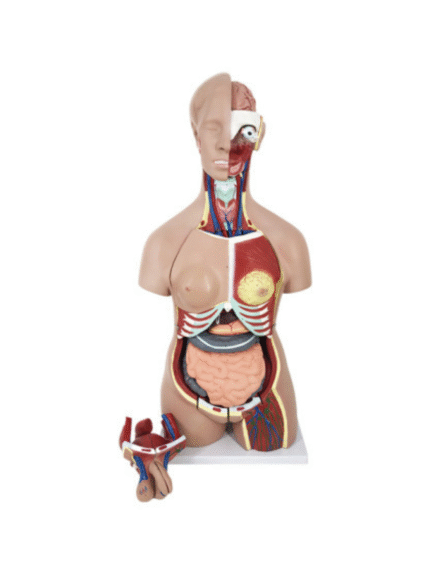

ATL-11 MALE MUSCLES FIGURE INTERNAL ORGANS HARD

The model is an anatomically accurate representation of the human anatomy, complete with superficial and deep musculature, the digestive system, lymphatic system, respiratory system, urinary system, circulatory system, endocrine system, and nervous system. Our model has removable organs and dissectible features for a complete educational experience.

Classification: